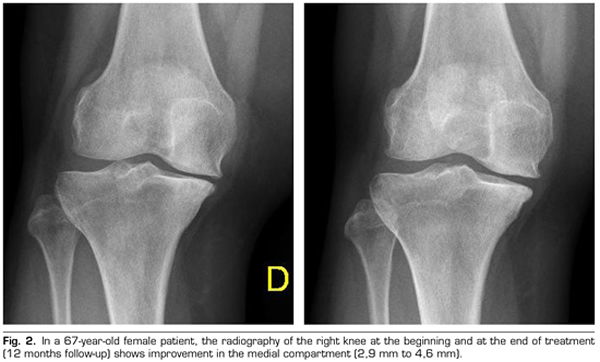

Figure 2

Radiological variables: In 53 patients analyzed radiologically (according to standardized protocol) at one year of follow-up after ozone treatment, the internal compartment increased significantly from 4.12 ± 1.41 mm to 4.4 ± 1.35 mm (p = 0.0008) and the external compartment increased from 6 ± 1.37 to 6.16 ± 1.4 mm (p = 0.0753).